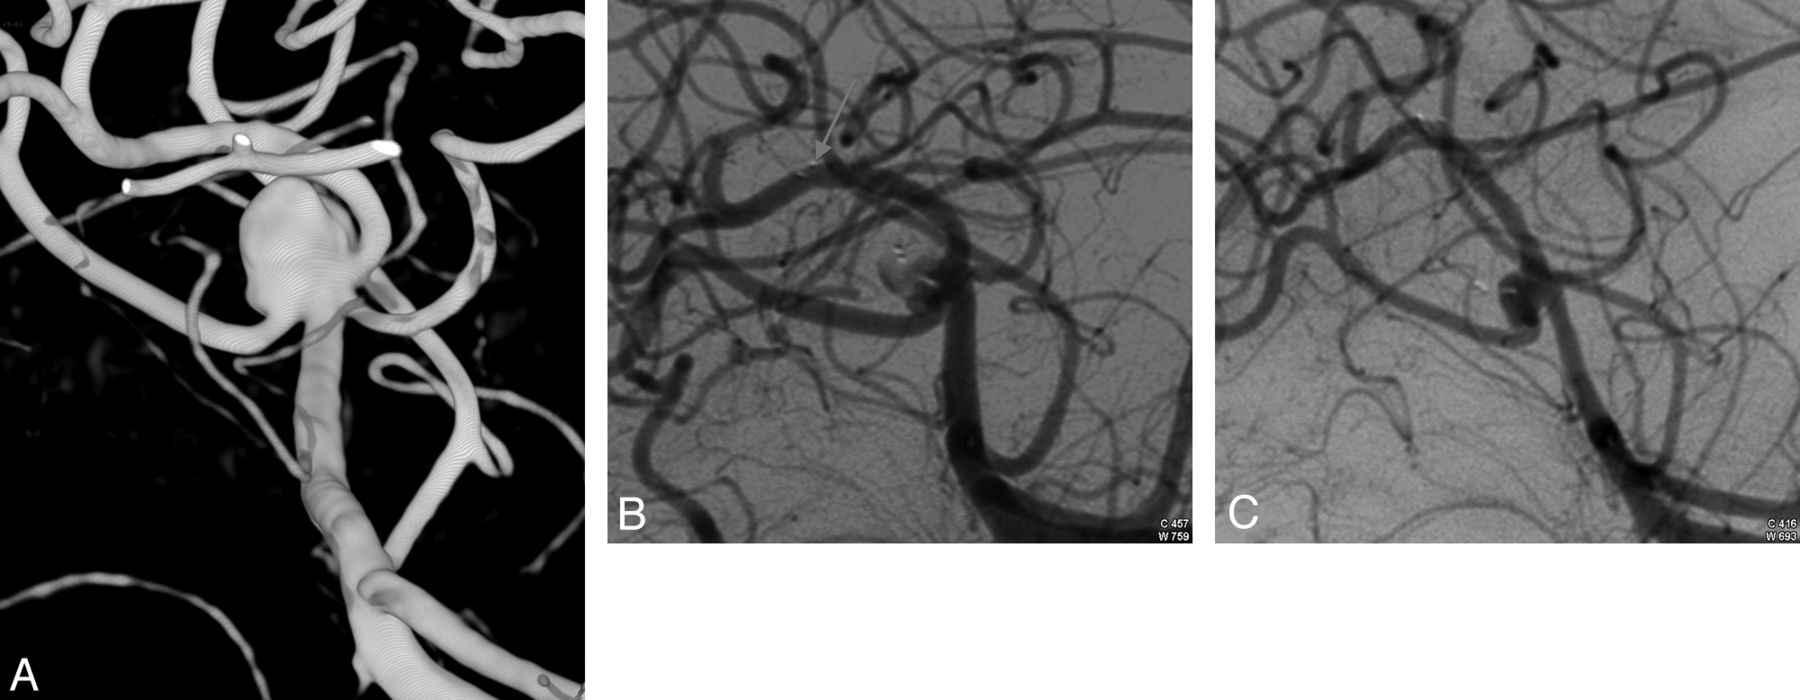

Case 3.

A 64-year-old woman (patient 7) presented with an incidental basilar tip aneurysm. Conventional angiography showed a 13-mm aneurysm with a 5-mm neck (Fig 3A). Endovascular treatment was performed by WEB placement, achieving an incomplete aneurysm occlusion (Fig 3B). Angiographic control at 3 months showed a stable occlusion, and further stent-assisted coiling was performed, achieving a complete occlusion (Fig 3C).

Incidental aneurysm in a 64-year-old woman. A, Conventional angiography shows a 13-mm basilar tip aneurysm with a 5-mm neck. B, Angiographic control at the end of EVT shows an incomplete aneurysm occlusion. C, Angiographic control after complementary treatment by stent-assisted coiling shows a complete aneurysm occlusion.